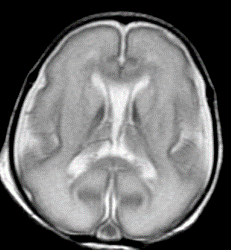

Структура (МРТ) головного мозга недоношенного на 15 недель ребенка (фото любезно предоставлено RSNA).

Доктор Блёмль и его коллеги изучали недоношенных детей, чтобы узнать больше о том, каким образом преждевременные роды способны привести к изменениям в структуре мозга, которые могут быть связаны с клиническими трудностями в дальнейшей жизни. Большая часть внимания была сосредоточена на белом веществе мозга, которое ответственно за передачу сигналов и обеспечивает связь между различными частями мозга. Поскольку некоторые повреждения белого вещества видны при структурной магнитно-резонансной томографии (МРТ), группа доктора Блёмля использовала МР-спектроскопию (МРС), чтобы увидеть различия на микроскопическом уровне.

В этом исследовании ученые сравнили концентрации некоторых химических веществ, характеризующих полностью развитое белое и серое вещество у 51 доношенного ребенка и 30 недоношенных детей. Исследовательская группа получила нормальные результаты при структурной МРТ, но сканы МРС показали значительные различия в биохимическом развитии белого вещества у доношенных и недоношенных младенцев, что свидетельствует о нарушениях в сроках и синхронизации развития белого и серого вещества. Серое вещество является частью мозга, которая обрабатывает и передает сигналы. "У этих недоношенных детей схема развития мозга нарушается, — говорит доктор Блёмль. — Развитие белого вещества началось раньше и было "рассинхронизировано" с развитием серого вещества".